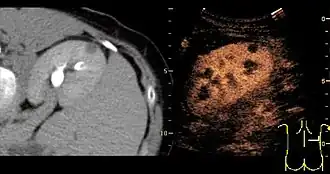

Kidney

Most renal cell carcinomas are now found incidentally.[19] Tumors less than 3 cm in diameter less frequently have aggressive histology.[20]

A CT scan is the first choice modality for workup of solid masses in the kidneys. Nevertheless, hemorrhagic cysts can resemble renal cell carcinomas on CT, but they are easily distinguished with Doppler ultrasonography (Doppler US). In renal cell carcinomas, Doppler US often shows vessels with high velocities caused by neovascularization and arteriovenous shunting. Some renal cell carcinomas are hypovascular and not distinguishable with Doppler US. Therefore, renal tumors without a Doppler signal, which are not obvious simple cysts on US and CT, should be further investigated with contrast-enhanced ultrasound, as this is more sensitive than both Doppler US and CT for the detection of hypovascular tumors.[21]